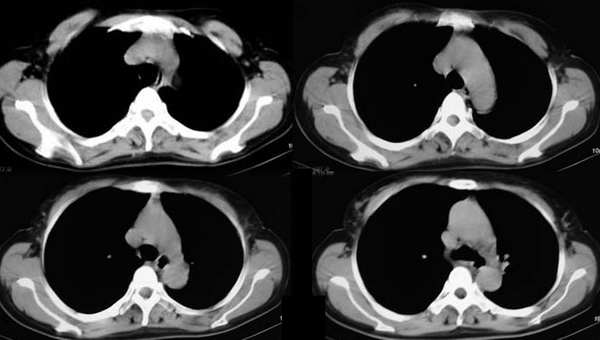

标题: CT2875:左下肺占位,请分析。

女,56y,左下肋缘下痛疼二月余

左侧胸廓容积缩小,纵隔左移,左下肺支气管闭塞.考虑中心型肺癌并左肺下叶不张,建议纤支镜.

属典型的左下肺中央型肺癌——左下分叶状肺肿块、支气管阻断、左下肺不张,纵隔淋巴结肿大。

左侧肺部体积缩小,纵隔向患侧偏移,左下肺支气管阻塞,中央型肺癌合并肺不张可能性大。

左下肺团块状软组织密度影,呈分叶状,边界清,未见小毛刺,左下肺支气管阻塞,纵隔见肿大淋巴结,考虑左下肺中央型肺癌伴纵隔淋巴结肿大,建议支纤镜检查。